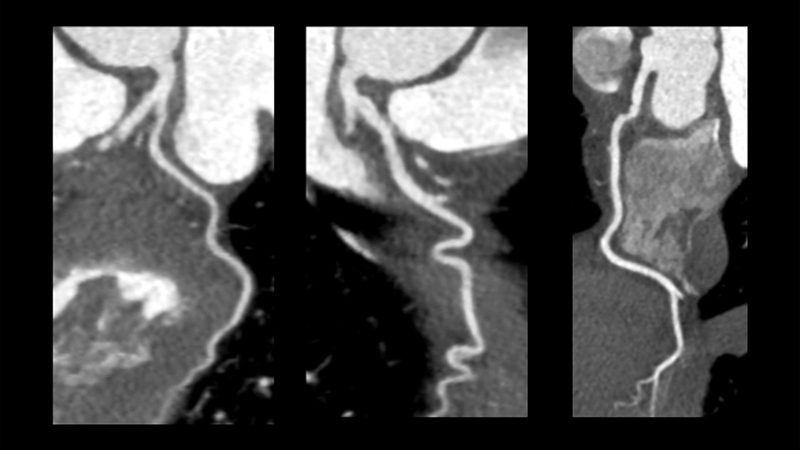

BT Anjiyografi

Evar protokolü ile hızlı koroner anjiyografi imkanı tanıyoruz.

• Daha az kontrast madde kullanarak vücuttaki tüm atar damarları yüksek kalitede görüntülüyoruz.

• Aynı anda roleout, koroner arterler ve pulmoner arterler görüntülemesini tek seferde, daha az kimyasal maddeyle renkli görüntülemesini yapabiliyoruz.